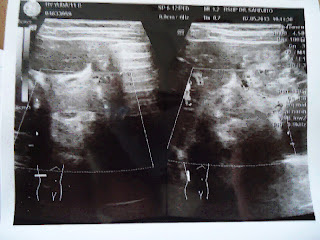

Pada USG Abdomen, didapatkan hasil mencurigakan seperti gambaran target sign/sausage sign.

Gambaran USG Abdomen